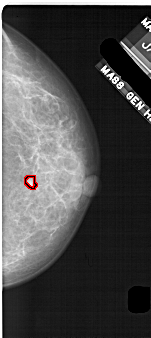

A_1708_1.RIGHT_MLO

A_1708_1.RIGHT_CC

RIGHT_CC LINES 5056 PIXELS_PER_LINE 2251 BITS_PER_PIXEL 12 RESOLUTION 43.5 OVERLAY

RIGHT_MLO LINES 5491 PIXELS_PER_LINE 2521 BITS_PER_PIXEL 12 RESOLUTION 43.5 OVERLAY

FILE: A_1708_1.RIGHT_MLO.OVERLAY

TOTAL_ABNORMALITIES 1

ABNORMALITY 1

LESION_TYPE MASS SHAPE IRREGULAR MARGINS ILL_DEFINED

ASSESSMENT 4

SUBTLETY 1

PATHOLOGY BENIGN

TOTAL_OUTLINES 1

BOUNDARY

FILE: A_1708_1.RIGHT_CC.OVERLAY